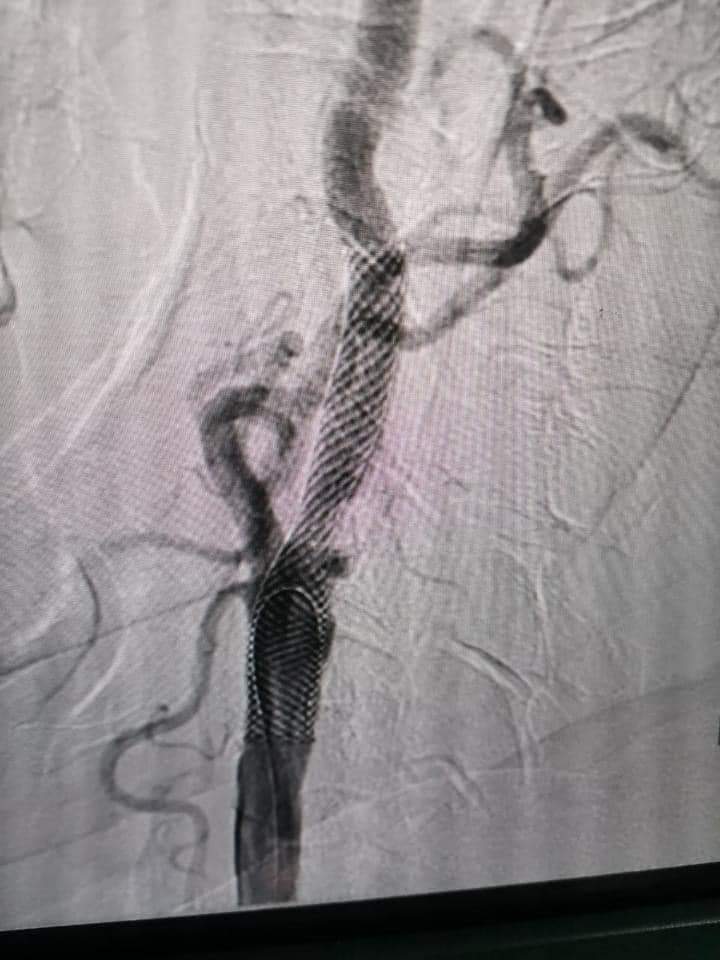

دعامة بـ الشريان السباتي

جاء ذلك من خلال تركيب دعامة ناجحة في الشريان السباتي للمريض، الذي كان يعاني من جلطات متعددة في المخ أدت إلى شلل نصفي أيسر نتيجة انسداد كامل لهذا الشريان.